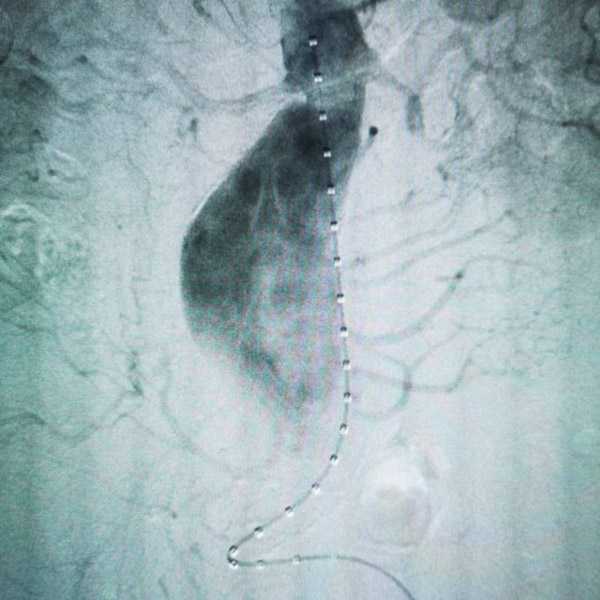

血管外科手術(shù)團(tuán)隊(duì)經(jīng)多學(xué)科會(huì)診后,決定先行冠脈造影及腦血管造影評(píng)估手術(shù)風(fēng)險(xiǎn)。評(píng)估后,決定為患者行雙腎動(dòng)脈體外預(yù)開窗+腹主動(dòng)脈腔內(nèi)修復(fù)。術(shù)中先行雙腎動(dòng)脈體外預(yù)開窗,然后在腹主動(dòng)脈內(nèi),精確將支架的雙開窗與雙腎動(dòng)脈開口位置對(duì)位,準(zhǔn)確釋放支架,并于雙腎動(dòng)脈處置入腎動(dòng)脈支架。

術(shù)后造影顯示腹主動(dòng)脈瘤完全隔絕,雙側(cè)腎動(dòng)脈血流通暢。一星期后復(fù)查CTA顯示支架位置良好,未見明顯內(nèi)漏,雙腎動(dòng)脈未見明顯狹窄或閉塞。